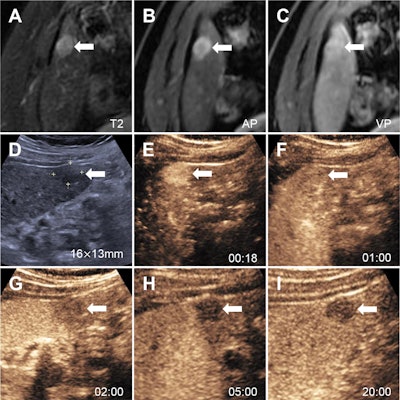

Images in a 52-year-old man with chronic hepatitis B show a nodule categorized as LR-3 at MRI using Liver Imaging Reporting and Data System (LI-RADS) version 2018 (A-C), as LR-5 at contrast-enhanced ultrasound (CEUS) using Strategy A (D-H), and as LR-5 at CEUS using Strategy B (D-I). At contrast-enhanced MRI, (A) an axial T2-weighted image in segment VI shows a 15-mm mildly hyperintense nodule (arrow). (B) The axial arterial phase shows hyperenhancement (arrow). (C) Axial portal venous phase image shows the observation with neither washout nor enhancing capsule (arrow). (D) Conventional gray-scale US in segment VI shows a 16-mm hypoechoic nodule (arrow). (E) Image shows arterial phase hyperenhancement (arrow) at 18 seconds. (F) Portal venous phase image at 1 minute shows no washout (arrow). (G, H) Late phase at 2 minutes (G) and 5 minutes (H) shows late and mild washout (arrows). (I) Kupffer-phase hypoenhancement at 20 minutes (arrow). Pathologic diagnosis based on surgical resection was hepatocellular carcinoma. AP = arterial phase, VP = venous phase.RSNA